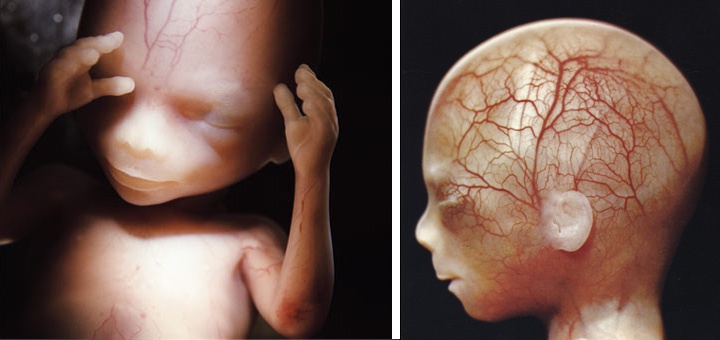

Фото: Леннарт Нильссон / TT

Плод в конце первого триместра.

Фото: Леннарт Нильссон / TT

Плод в начале второго триместра.

Фото: Леннарт Нильссон / TT

Плод в конце второго триместра.

Фото: Леннарт Нильссон / TT

Плод в конце третьего триместра.

Фото: Леннарт Нильссон / TT